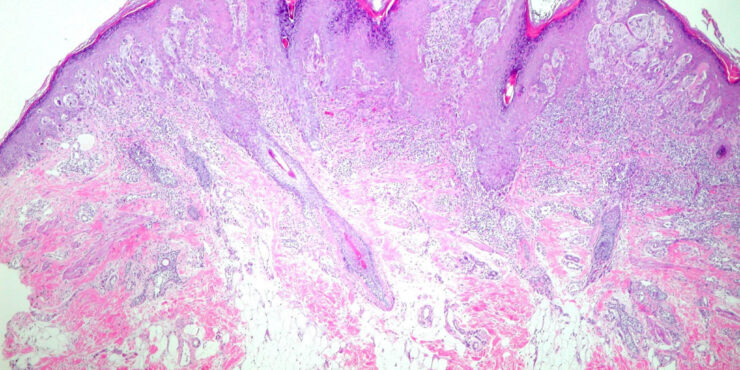

Read MoreSpitz tumor (malignant Spitzoid neoplasm–Metastasizing = ورم سبيتز